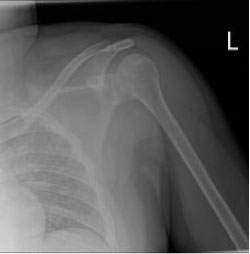

Radiograph of the right shoulder taken in the anterior-posterior approach showed a fractured lesser tuberosity found to be displaced caudal to the glenoid (Figure 1). The axillary view clearly revealed an isolated avulsion fracture of lesser tuberosity of the left humerus (Figure 2).

Figure 1: Showed a fractured lesser tuberosity displaced caudal to the glenoid. View Figure 1